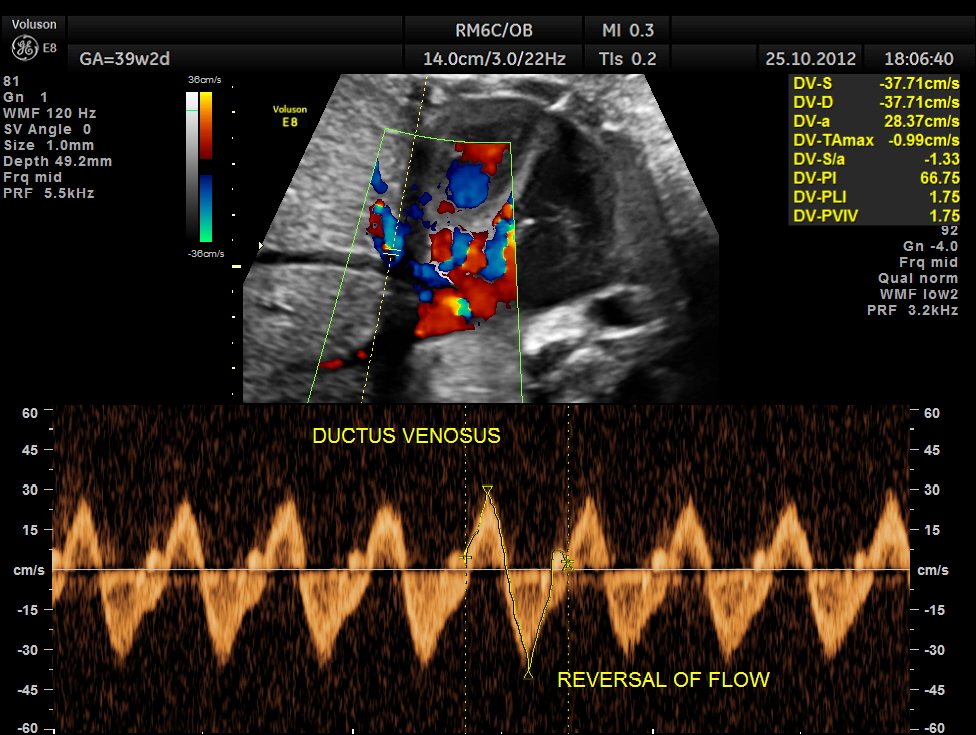

THIS FETUS HAD SEVERE FETAL ANEMIA WITH CARDIAC FAILURE LEADING TO CARDIOMEGALY WITH MITRAL, TRICUSPID AND PULMONARY REGURGITATION .NO OTHER OBVIOUS CARDIAC ANOMALY WAS MADE OUT . THE VENO ATRIAL , ATRIO VENTRICULAR AND VENTRICULO ARTERIAL CONCORDANCE APPEARED TO BE NORMAL; NO SEPTAL DEFECT WAS MADE OUT.